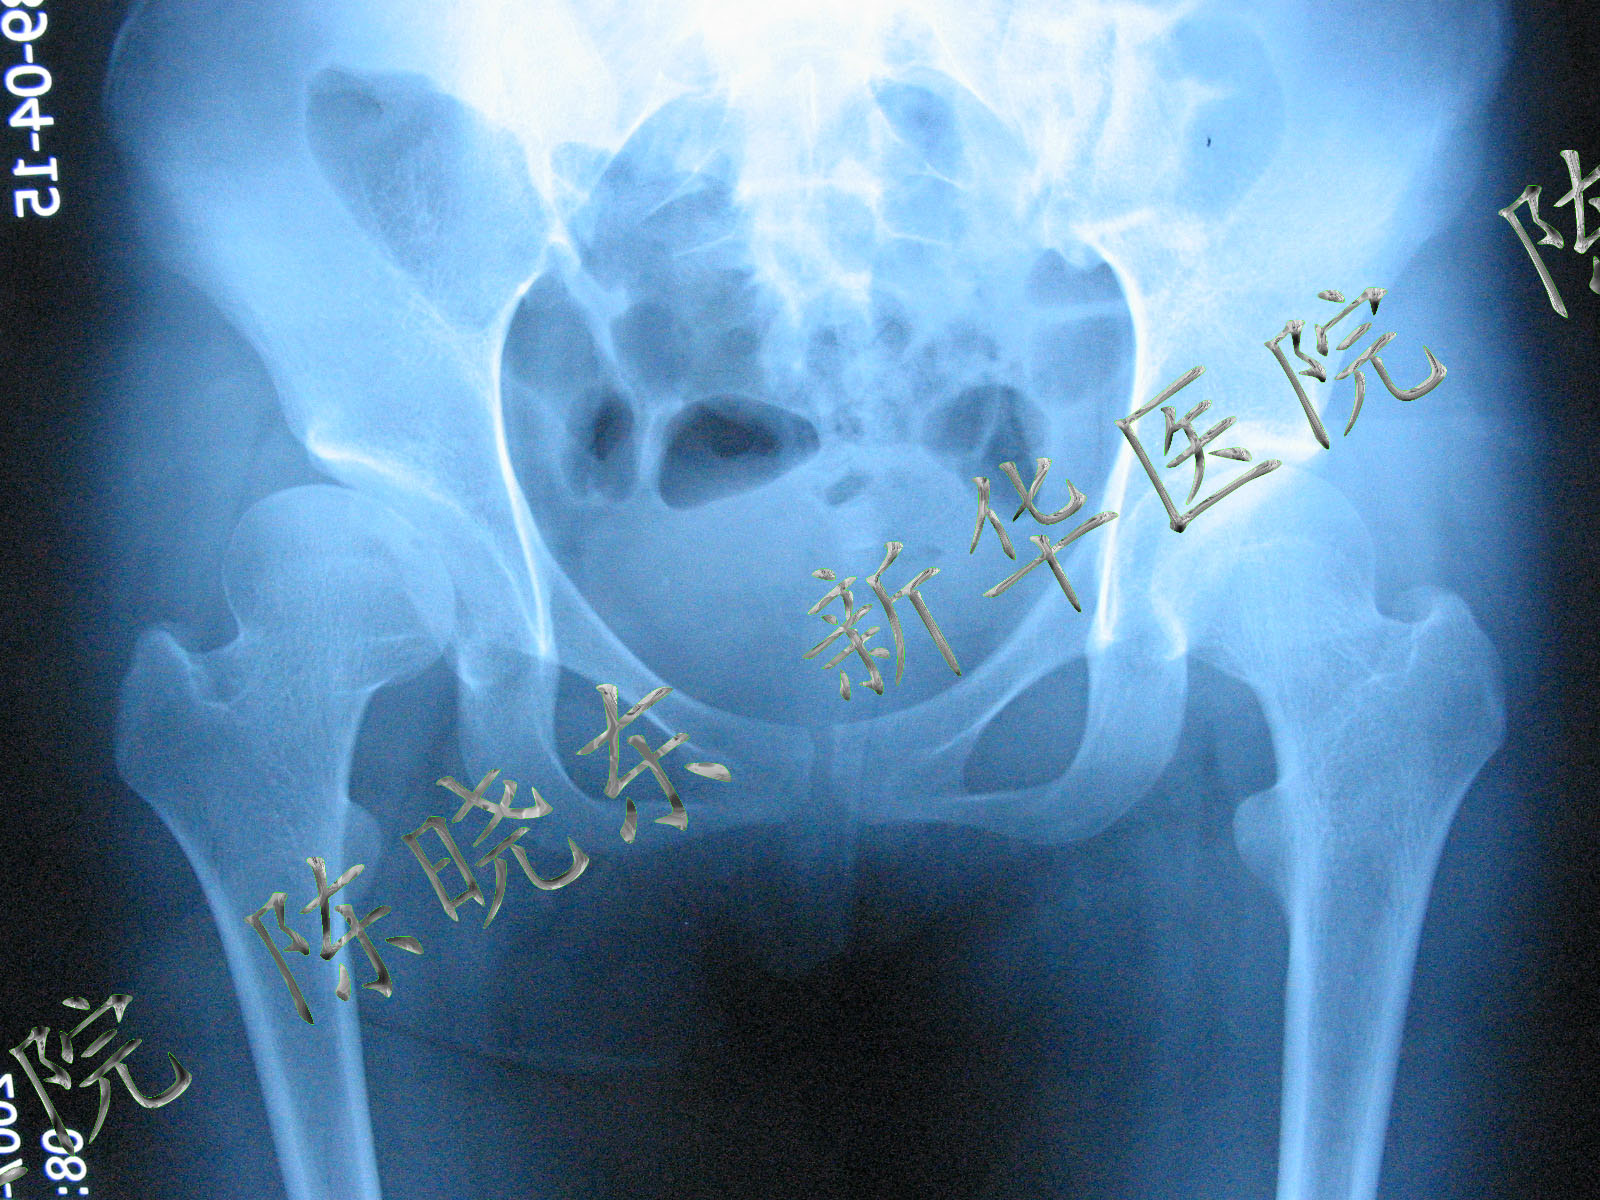

一例陈旧髋关节半脱位并股骨头部分缺损,大家看看

图片尺寸2448x3264